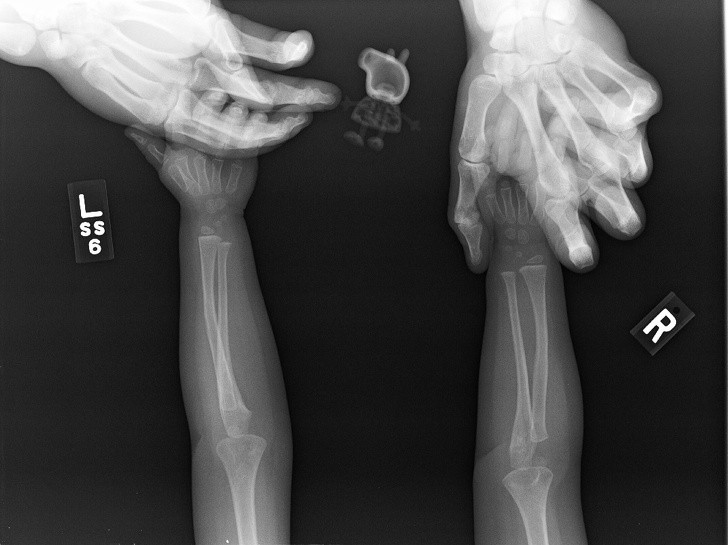

Rentgen je eden najboljših izumov človeštva in v nekaterih situacijah je nepogrešljiv. Še posebej zato, ker se velikokrat zgodi, da ljudje, še posebno otroci, požirajo predmete, ki niso del dnevne prehrane. Da ne omenjamo psov, ki poskušajo prežvečiti vse, kar vidijo, in tako velikokrat pogoltnejo neprimerne stvari.

Radiologi so tako že precej navajeni, da na rentgenskih posnetkih vidijo čudne stvari in nekatere izmed teh, ki smo jih za vas zbrali v galeriji, jih sploh niso presenetile. Tukaj je 15+ odštekanih in na trenutke šokantnih rentgenskih posnetkov.